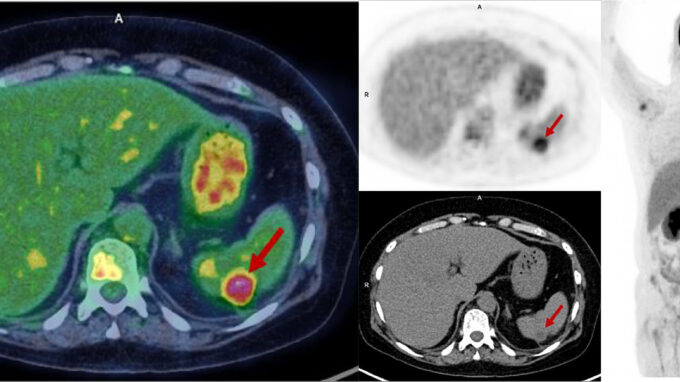

Tecnología Médica